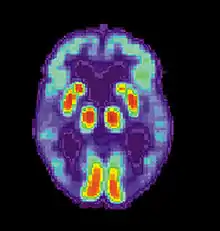

Obsessive compulsive disorder

Neuroimaging studies show that OCD patients perform considerably better on procedural memory tasks because of noticeable over-activation of the striatum brain structures, specifically the frontostriatal circuit. These studies suggest that procedural memory in OCD patients is unusually improved in the early learning stages of procedural memory.[69] However, another study found that individuals with OCD do not perform significantly different on procedural working memory tasks than healthy controls.[27] Differences between the two studies may be due to the different procedural memory tests that were used and the different aspects of procedural working memory they may be tapping on. Specifically, the study which found improved performance in early stages of procedural memory employed a pursuit rotor task, whilst the study that found no differences in procedural memory between controls and OCD participants used a choice reaction task.